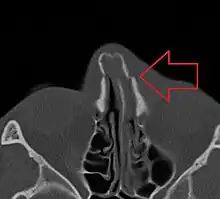

Nasal bone fracture

Bilateral nasal fracture as seen on CT scan